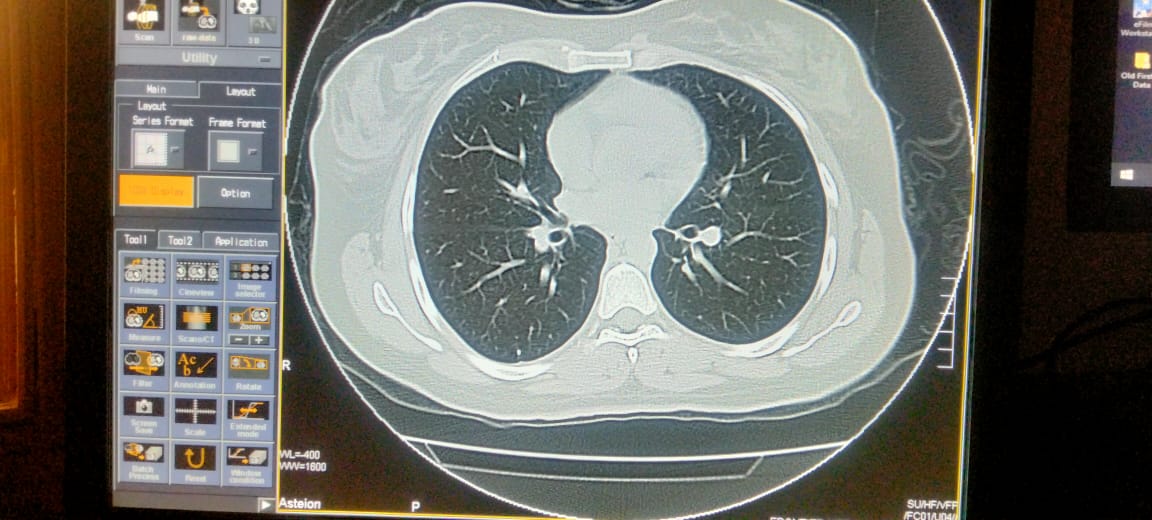

Plz describe it. Film of hrct of corona patient

Send full films, its incomplete